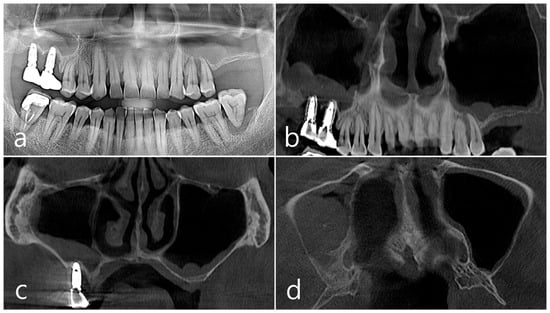

2.2. Case 2

This patient was a 58-year-old male smoker who was taking antihypertensive drugs. The patient visited our clinic for implant placement in the upper left posterior region. Teeth #24 and #25 were determined to be extracted due to severe periodontal disease. In panoramic radiography, the residual alveolar bone was severely atrophied, and pneumatization of the maxillary sinus was severe (Figure 7a). In CBCT imaging, membrane thickening was observed in the sinus floor, but there was no membrane thickening in the rest of the sinus wall (Figure 7b–d).

Figure 7. Case 2. (a,b) On the preoperative panoramic radiography and panoramic image of CBCT, the residual alveolar ridge in the posterior maxilla was severely atrophied and pneumatization of maxillary sinus was severe; (c,d) In CBCT imaging, mucosal thickening (arrows) ranging from 2 to 15 mm was observed in the sinus floor, depending on the location, but there was no mucosal thickening in the rest of the sinus wall.